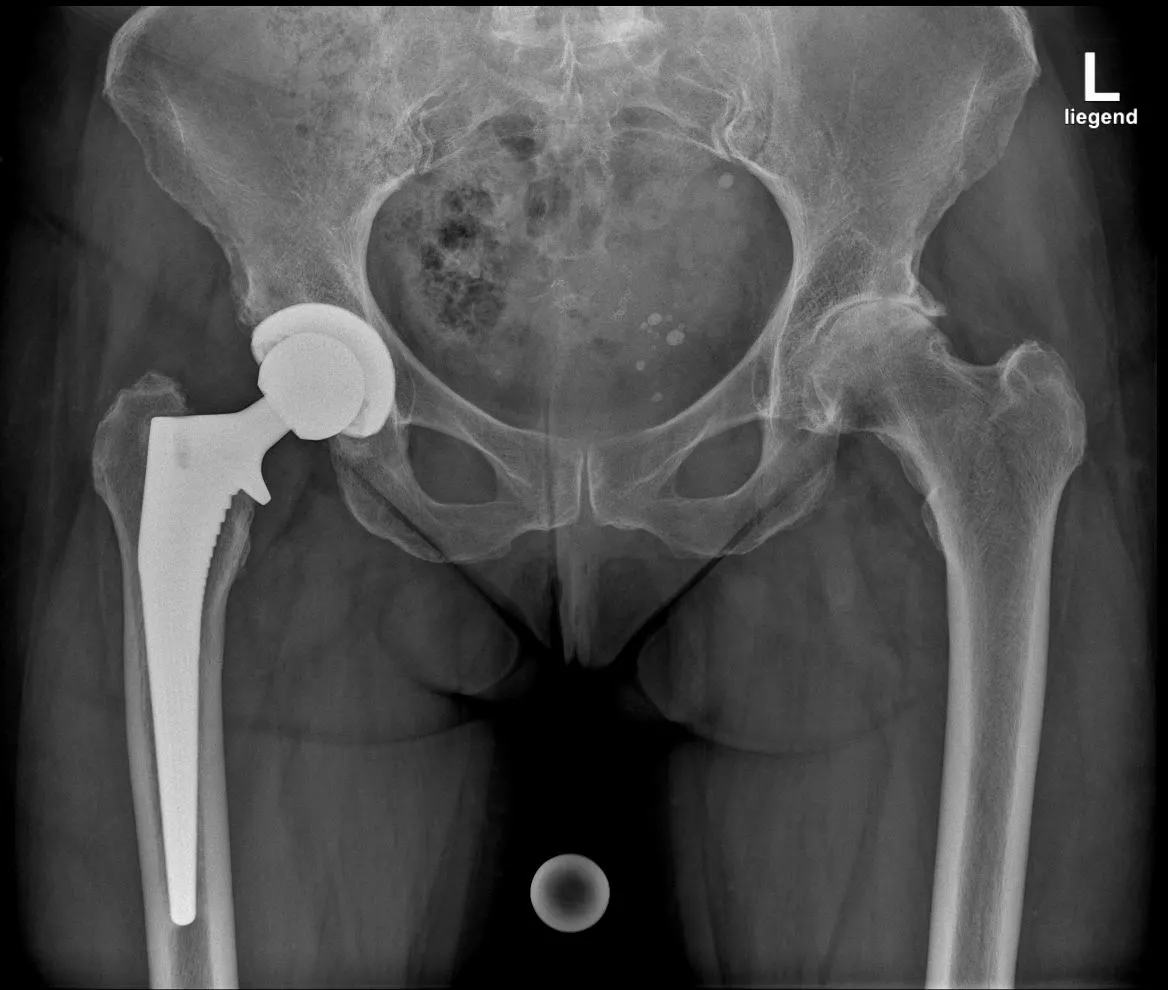

Röntgenbild einer Coxarthrose präoperativ

Hüftprothese Postoperativ